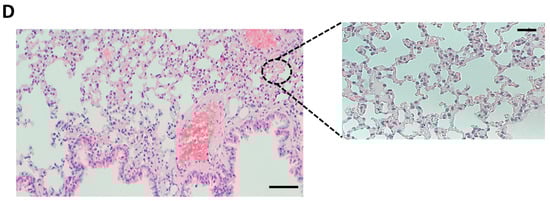

2.5.2. Histological Analyses

3.2. SSi6 Doses No Provoke Toxic Effects on FVB Mice